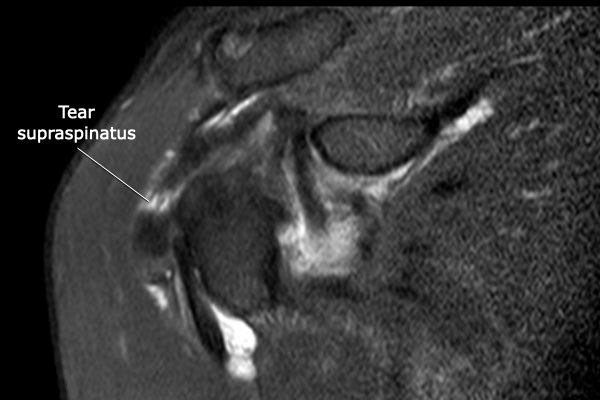

Rách toàn bộ chiều dày

Rách toàn bộ chiều dày (Full Thickness Tear – FTT) là tổn thương kéo dài từ mặt túi hoạt dịch (bursal surface) xuyên suốt đến mặt khớp (articular surface).

Rách toàn bộ chiều dày không hoàn toàn

Dấu hiệu đặc trưng trên MRI của rách toàn bộ chiều dày không hoàn toàn là khe hở chứa đầy dịch trên chuỗi xung T2W.

Có hình ảnh rách toàn bộ chiều dày không hoàn toàn, kích thước nhỏ tại phần xa của gân cơ trên gai, không có co rút.

Có một số hình thành nang tại đầu xương cánh tay ở vị trí bám tận, kèm theo phản ứng túi hoạt dịch và tăng tín hiệu trong gân do viêm gân (tendinosis).

Có hình ảnh rách toàn bộ chiều dày phần trước của gân cơ trên gai, kéo dài từ mặt khớp đến mặt túi hoạt dịch.

Do các sợi gân phía sau của gân cơ trên gai còn nguyên vẹn, tổn thương này được gọi là rách toàn bộ chiều dày không hoàn toàn của gân cơ trên gai.

Không có co rút.